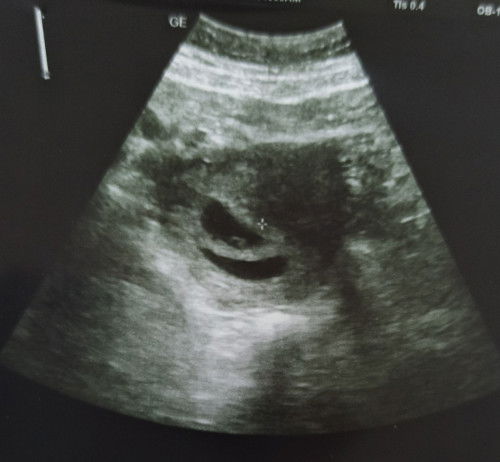

8w baby twin ( normal ke 1 je nmpk kntung )

Ade ke yg mcm Sy ye , 8w scan 2 kntung , 1 kntung nmpk cantik Ade janin , 1 lgi kosong dn kntung tak brpa cntik 🥲, bulan 12 thun LPs Sy keguguran , berhrap sngt tahun ni dpt bby , tak sngka plk twin sbb kmi xde keturunan twin dn Sy bru 24thn , minggu dpn Sy nk bt TVS scan doakn Sy dh boleh nmpk bby 😔 lma ttc ni 4thn